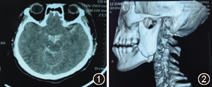

患者女性,20岁,因"交通事故致头面部外伤3 h"就诊。患者受伤时昏迷约10 min,清醒后自觉头痛、头晕、恶心伴左面部肿胀、疼痛及张口困难。神经外科检查:生命体征平稳,神志清楚,对受伤情况不能回忆,神经系统检查未见明显异常,格拉斯哥昏迷评分(glasgow coma scale, GCS)15分。口腔颌面外科检查:左侧下颌角区肿胀,压痛明显,开口度1.0 cm,咬合关系紊乱,左后牙早接触,前牙开

。CT检查:环池蛛网膜下腔高密度影、颅底骨折,左侧下颌角骨质连续性中断(图1,图2)。

诊断:脑挫裂伤、蛛网膜下腔出血、颅底骨折、左侧下颌角骨折。

治疗过程:当时存在明显的颅脑损伤,神经外科给予脱水、止血、神经营养等对症治疗。4 d后患者头痛、头晕明显减轻。复查CT示蛛网膜下腔出血大部分消失。因合并颅脑损伤,因此下颌骨骨折选择保守治疗。外伤后8 d患者头痛、头晕症状完全消失,口腔颌面外科在局麻下行"上下颌牙弓夹板固定、颌间牵引复位术",在结扎固定过程中患者突然口唇发紫、呼吸急促、随后全身抽搐、意识丧失、呼吸停止,全过程持续约3 min。迅速心肺复苏,1 min后自主呼吸恢复,双侧瞳孔散大,中度昏迷,右侧肢体偏瘫、肌力Ⅰ级,GCS 9分。急查头颅CT示脑室、脑干继发出血。立即给予脱水、止血及促醒等治疗,但昏迷进行性加重,颅内压600 mmH2O(正常值80~180 mmH2O)。补充诊断:脑室、脑干继发出血、颅内压增高。陆续施行脑室外引流及脑室-腹腔分流等手术,但效果不佳,外伤后3个月死于呼吸、循环系统衰竭。